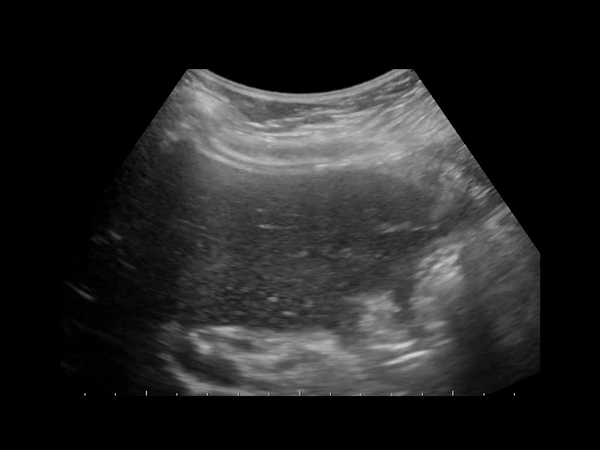

Увеличенный желчный пузырь выявляется при пальпации области правого подреберья – определяется болезненное либо безболезненное округлое образование. Однако, пальпация не позволяет установить точные размеры органа, особенно у ребенка. Поэтому обязательно проводится инструментальная диагностика. Обнаружить отклонения в размерах органа и выявить функциональные нарушения его работы можно с помощью УЗИ.

Ультразвуковое исследование – информативный метод, позволяющий поставить точный диагноз. При этом УЗИ является самым безопасным способом диагностики, при необходимости его можно проводить даже для обследования новорожденного.

С помощью УЗИ помимо увеличения размеров органа можно обнаружить:

- утолщение либо истончение стенок, включения в просвете желчного пузыря (обычно при холецистите и жкб);

- нарушение сократительной способности органа (при дискинезии желчевыводящих протоков);

- сужение или перекручивание желчных протоков, перегиб шейки пузыря (у детей, как правило, обусловлены врожденными структурными аномалиями, у взрослых чаще являются приобретенными);

- расширенный общий желчный проток (отмечается при жкб и стенозирующем папиллите);

- растяжение пузыря, утолщение его стенок свыше 5 мм, жидкость внутри органа (обнаруживаются при эмпиеме – скоплении в полости желчного пузыря большого количества гнойного содержимого);

- растяжение без утолщения стенок, жидкость внутри (развиваются при мукоцеле – слизистой кисте);

- обструкция желчевыводящего протока, утолщение стенок пузыря (может свидетельствовать о глистной инвазии, когда гельминты перекрывают желчный проток, препятствуя оттоку желчи либо о воспалении головки поджелудочной железы, при этом утолщение стенок пузыря может быть признаком нагноения);

- доброкачественное или злокачественное образование, полипы.

Центральная задача УЗИ — отличить катаральную и деструктивную форму острого холецистита.

При катаральном воспалении стенка диффузно утолщена, перипузырный жир эхогенный (отек).

При деструктивной форме толстая стенка с дефектами, в просвете слизистые псевдомембраны.

При перфорации дефект стенки сквозной, вокруг пузыря разливается жидкость, нередко камни.

При эмфиземе эхогенный газ отражает ультразвук и дает «грязную» заднюю акустическую тень.

Тень не чисто анэхогенная (как в случае желчных конкрементов), а промежуточной эхогенности.